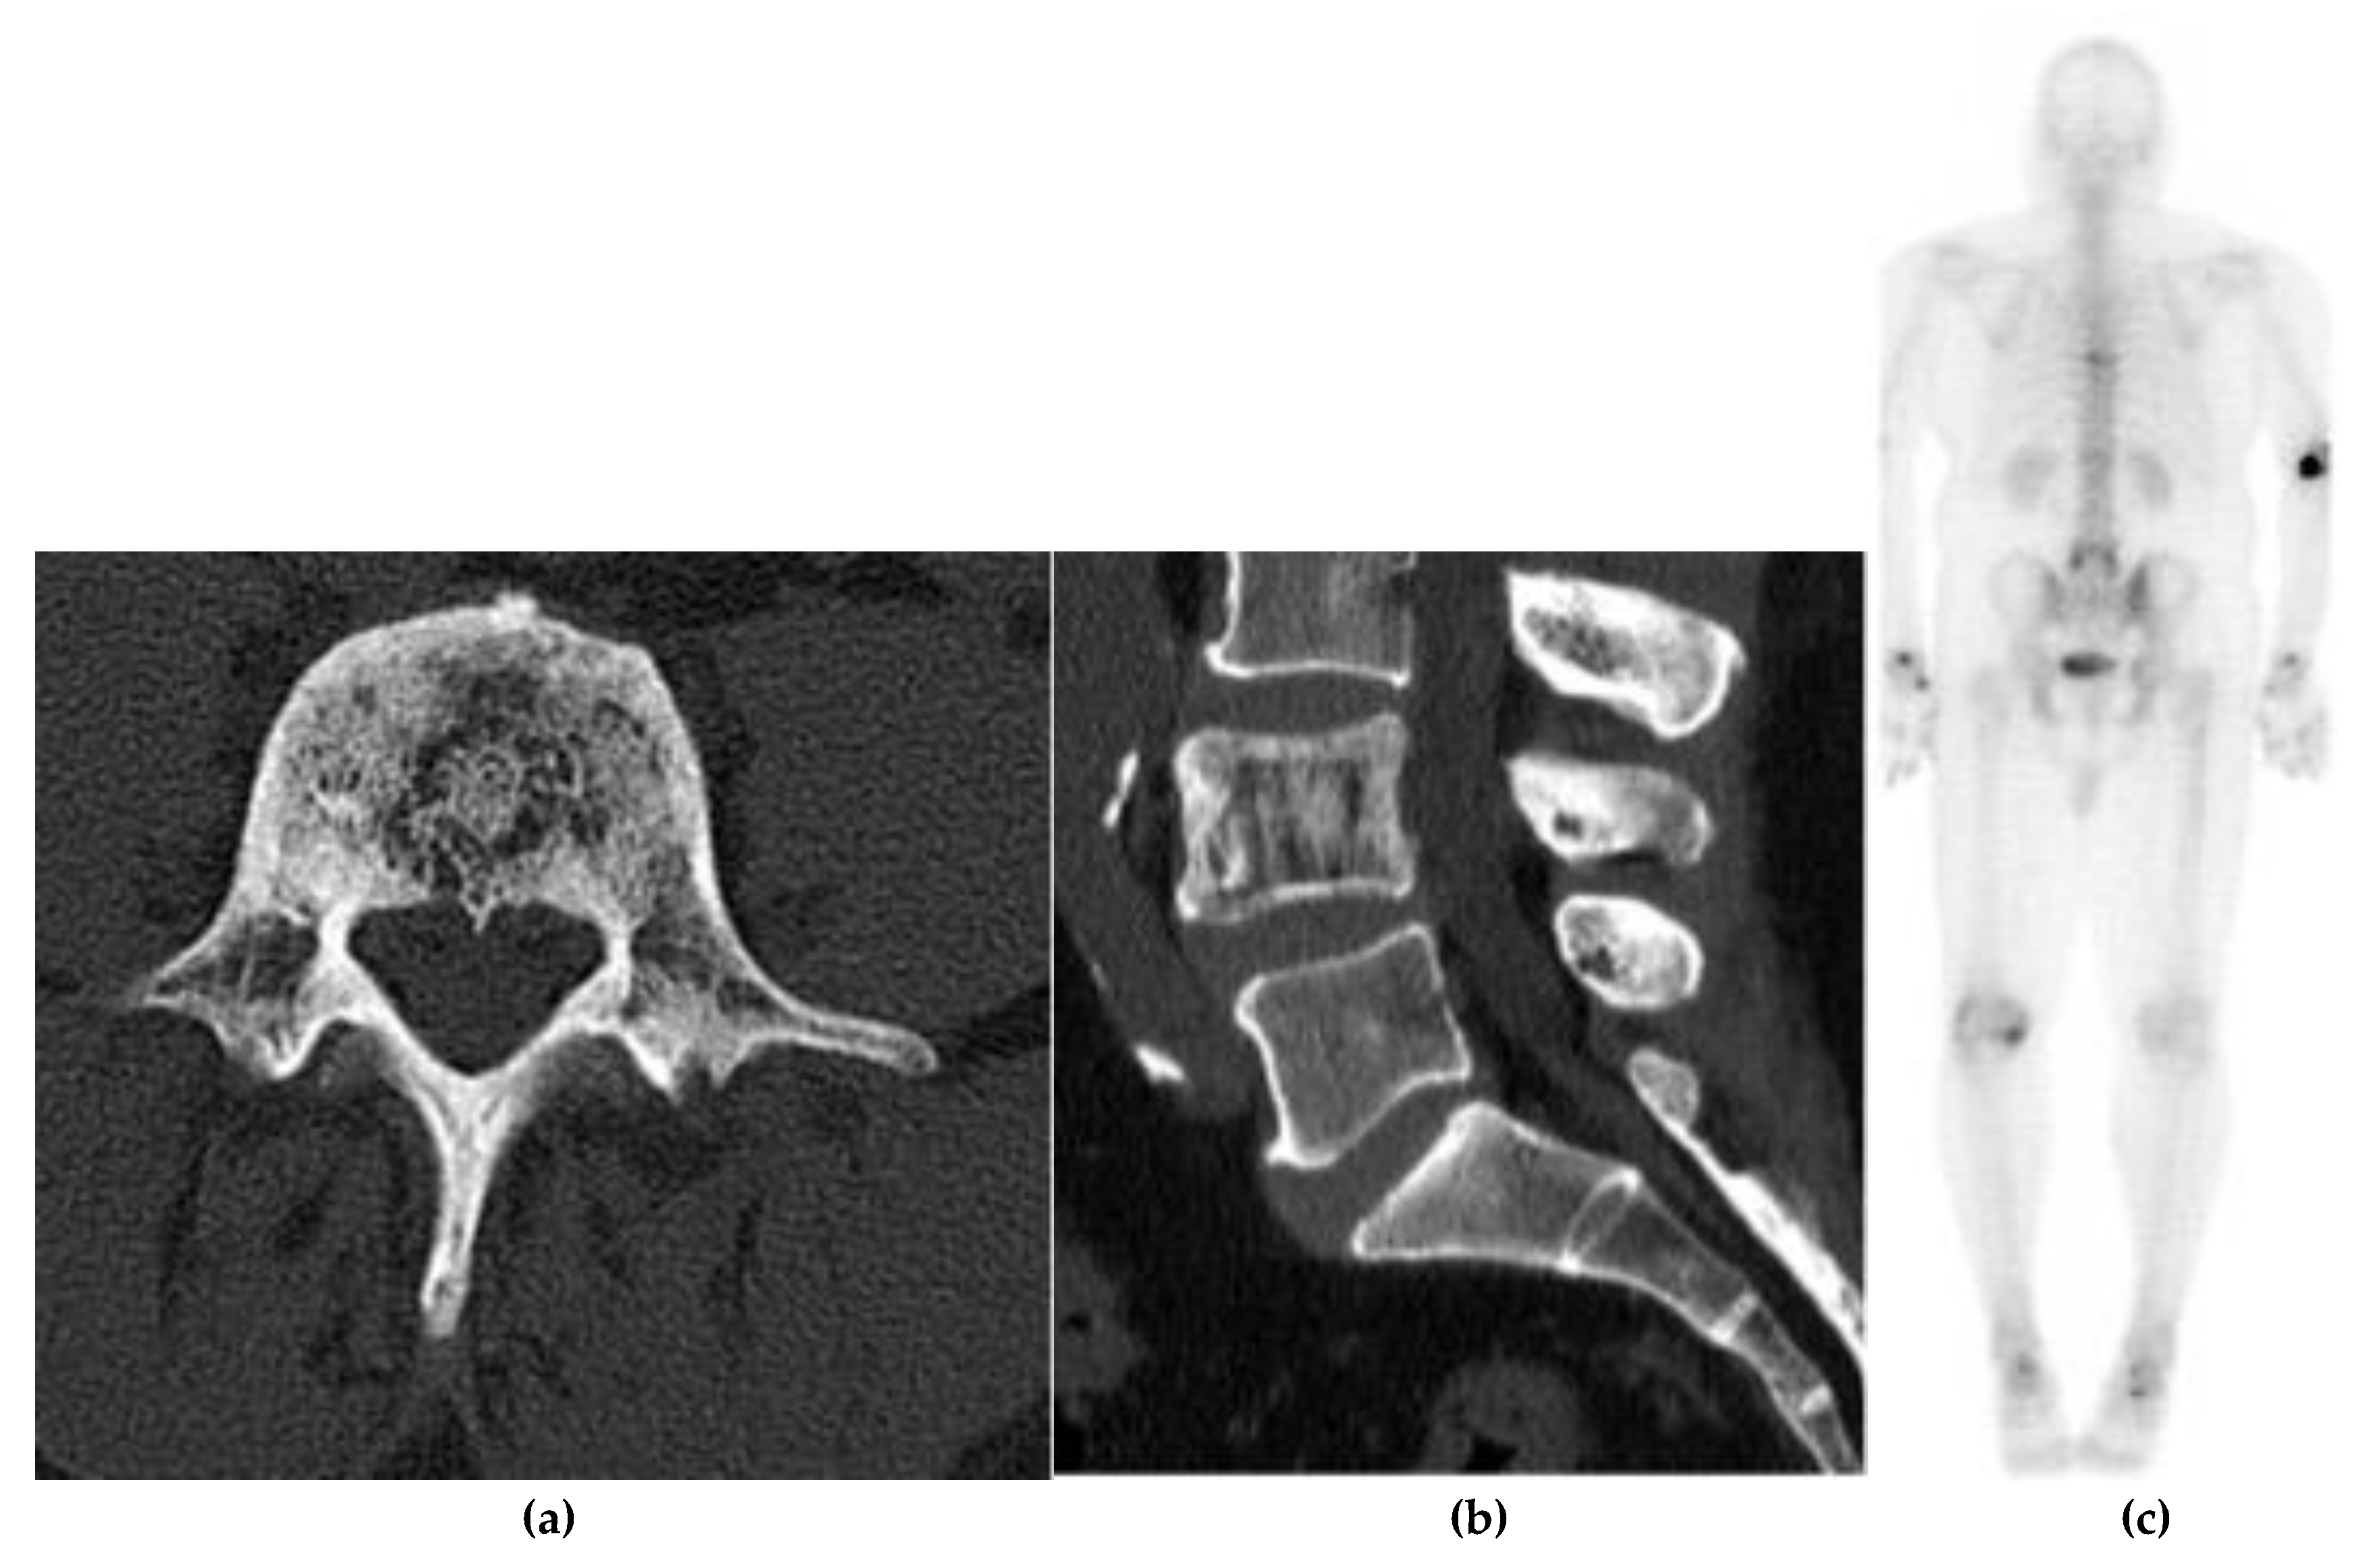

Ewing Sarcoma